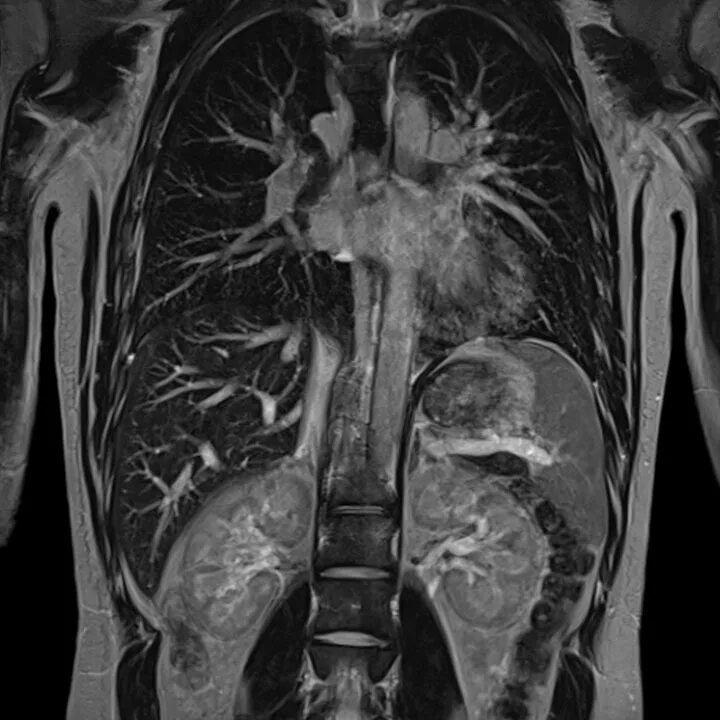

Что показывает мскт